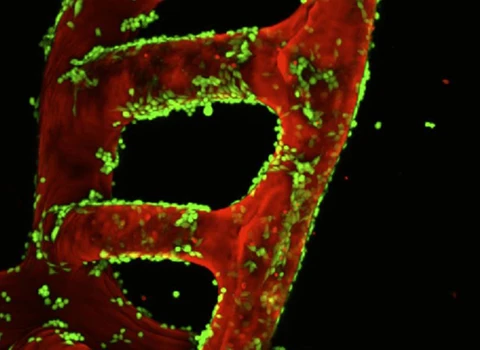

La ingeniería regenerativa es un campo nuevo y emocionante que se define como la convergencia de los avances en la ciencia e ingeniería de materiales, células madre y biología del desarrollo, ciencias físicas y la aplicación clínica para desarrollar herramientas escalables y confiables que permitan la regeneración ó reconstrucción de tejidos complejos y órganos. Puede considerarse un campo que busca facilitar la implementación de la medicina regenerativa para todos.

Con este objetivo, profesores de la Escuela de Ingeniería McCormick y de la Escuela de Medicina Feinberg convergen para participar en investigaciones y educación a través del Instituto Querrey Simpson de Ingeniería Regenerativa de la Universidad Northwestern (QSI RENU), que liderará la iniciativa para desarrollar y traducir tecnologías transformadoras que capaciten a nuestro cuerpo para sanar.